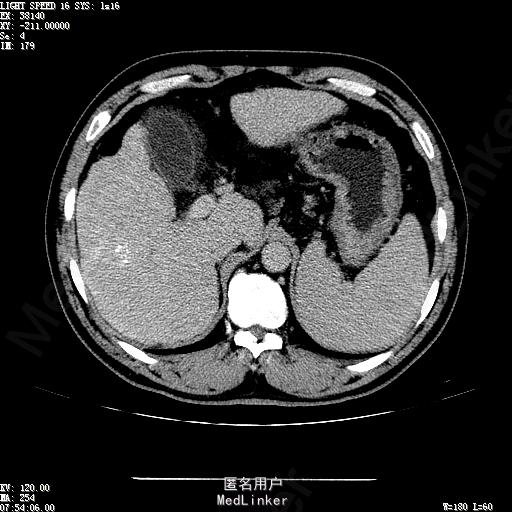

主诉:肝癌TACE治疗后36天 病史:患者两年前体检发现丙型肝炎病毒标志物阳性,于当地医院就诊诊断为"丙肝肝硬化",口服药物治疗,具体用药不详。定期复查肝功及肝脏影像学检查,2月前于医大二院行肝脏增强磁共振检查发现肝S6段动脉期增强结节,36天前在我院行DSA肝动脉造影明确"原发性肝癌"诊断并行"TACE"治疗,术后恢复良好,现患者为进一步行肝癌局部消融治疗来诊。

诊断:1、丙肝肝硬化 代偿期;2、原发性肝癌 S5段、S6段 该患诊断明确,既往曾行TACE治疗肝癌,S5段、S6段近右肾上极2处碘油沉积明确,S5段者较大,约2.31cm。超声显示清晰,为防止癌灶复发,适合行射频消融治疗。